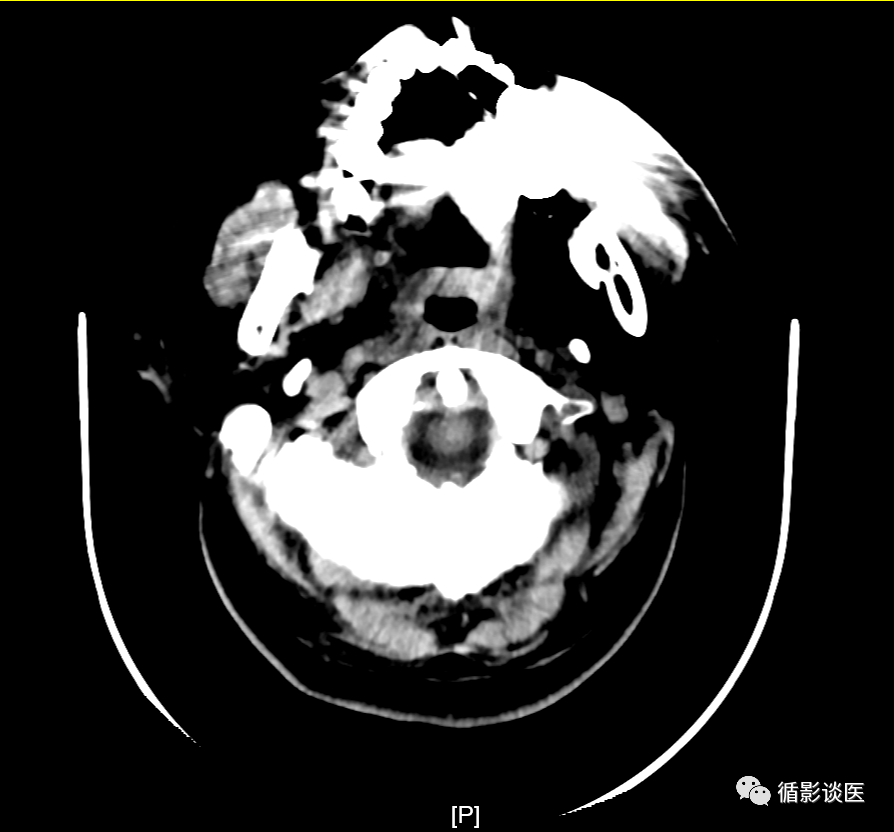

如图:头颅扫描时,金属假牙在虽然有放射状伪影但不影响颅内病变显示。